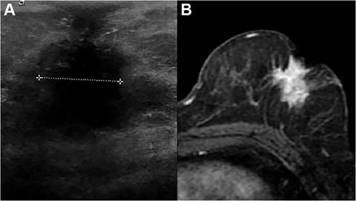

La ecografía es una herramienta complementaria muy útil en el estudio de la patología mamaria, por sus características de fácil accesibilidad y ausencia de radiación ionizante. Se utiliza como un examen dirigido para evaluar los hallazgos observados en la mamografía o en la RM,(22) es de gran utilidad como guía para procesos intervencionistas(23) y en la evaluación inicial de mujeres menores de 30 años o embarazadas con un nódulo palpable. (24) En relación con la valoración de la región retroareolar, la ecografía proporciona una excelente resolución espacial superficial, (12) mejorando la detección de lesiones de pequeño tamaño. Se ha publicado que la ecografía es un predictor significativo de la afectación del pezón en el cáncer de mama. (13) Para la evaluación del CAP se recomienda el empleo de abundante cantidad de gel y de una almohadilla de separación, para disminuir los artefactos producidos por la estructura del pezón.(25) El objetivo principal de la evaluación ecográfica del CAP se centra en la detección de nódulos solidos retroareolares, engrosamiento del CAP o de la piel circundante, lesiones solidas intraductales y la búsqueda de lesiones quísticas con contenido sólido adyacentes al CAP. La ecografía es de gran utilidad para confirmar o descartar el origen quístico de nódulos retroareolares. Las lesiones sólidas subareolares o intraductales pueden identificarse más fácilmente que en la mamografía.(22) Se pueden observar pseudolesiones en mujeres con ectasia ductal con contenido en su interior, en ductos tortuosos o curvos, o ductos con fibrosis intraductal y periductal en mujeres con ectasia ductal crónica.(26) Los tumores que contactan o invaden el pezón visualizados ecográficamente se correlacionan significativamente con el compromiso del CAP13 (Figura N° 2). La ecografía Doppler apoya la caracterización de lesiones sólidas visualizando flujo vascular en su interior. Cuando se detecta una anormalidad indeterminada es de gran utilidad la comparación con la mama contralateral.

Fuente. Propia

Figura N° 2 A) Ecografía mamaria izquierda. Neoplasia mamaria que invade el pezón. B) Resonancia magnética, secuencia T1 postcontraste contraste de la misma paciente. Realce tumoral homogéneo retroareolar con extensión al CAP. Diagnóstico anatomopatológico: Carcinoma ductal apocrino infiltrante con invasión del pezón